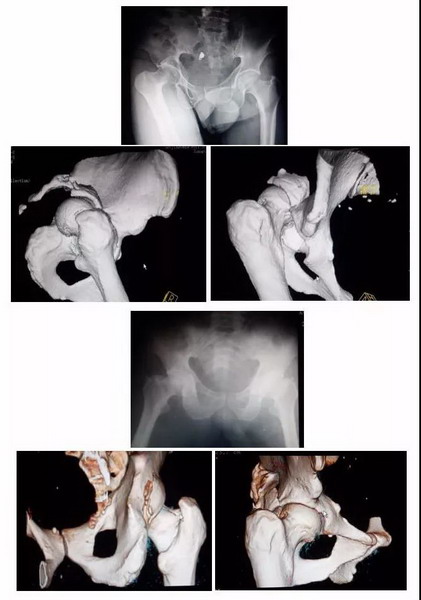

3D打印技术能让骨科手术实现“私人订制”

市民李先生因严重车祸导致全身多处受伤,其中髋臼(盆骨附近)骨折。常规手术需要选择医用钢板、螺钉等置入物,由于置入物是按一定规格批量生产,因此骨科医生只能依靠经验来选择最适合的,或现场进行塑型,调整成较为合适的尺寸。这样就使得手术时间长,复位固定过程难度很大。再加上髋臼周围的内外侧面有大量肌肉附着,并且有血管网形成,因此,手术难度系数较大。在江门市五邑中医院骨二科,医生借助3D打印技术,按照1:1的比例打印出完全相同的骨盆髋臼骨折模型,提前为患者选择适合的医用钢板、螺钉。术前进行模拟手术,提高手术效率,患者术后恢复良好。

区文欢主任说,借助3D打印技术,医生可以将患者CT扫描的数据,通过专用的软件分析,整合出患者关节组织全仿真信息,1:1打印出来,实现多维模拟,准确测量数据、设计手术方案。同时,利用计算机技术将骨折进行复位,然后再打印出一个复位好的1:1模型,在模型上进行内固定的预塑形,使内固定更贴合。这样可以节省时间、优化流程,使手术更精准,创伤也更小,减少手术感染几率。精准的钢板塑形还能使骨折端的复位不易丢失,特别在复杂的关节周围骨折、骨盆骨折、肩胛骨骨折等,应用3D打印技术有显著优势。

目前3D打印技术的辅助应用,主要是骨科中相对复杂、精细的手术,如骨盆骨折、髋臼骨折、上下肢复杂关节内骨折,以及复杂髋、膝关节翻修等。对外地患者的会诊,医院骨科也可以通过对方医院传来的患者影像数据,借3D打印机打印出仿真模型,以此为手术提供远程指导。“自2015年在我院应用以来,3D打印技术越来越成熟,在骨科领域的应用范围也越来越广泛,越来越多患者享受到这项技术带来的好处。”区文欢主任表示。